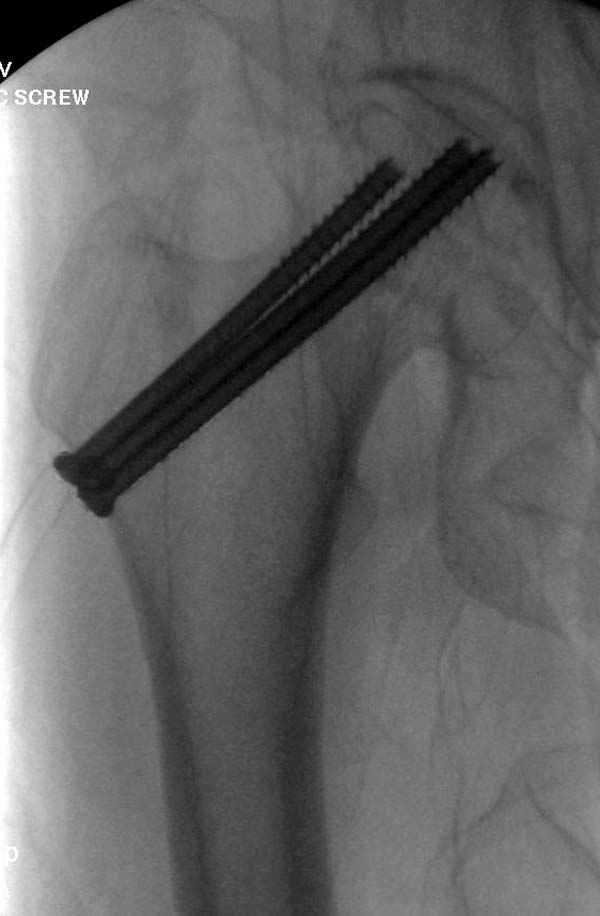

На второй день после выписки упал дома. Снимки приложены. Коллеги рекомендуют удаление шурупа и вытяжение. Что делать?

Наверное речь идет насчет parallel guide из набора. Применяем по возможности всегда, но,

как видно на снимке, не всегда получается

паралельно.

Такие несмещенные переломы обычно для молодых резидентов, и бывают технические неточности, но в этом случае посчитали фиксацию адекватной.

Соблюдая правила, многократными попытками можно

увеличить риск стрессового перелома латерального

кортекса.

Правильно, ситуация изменилась, как говорят у нас теперь "different animal", надо решать проблему подвертельного перелома. При наличии различных вариантов фиксаторов, включая Страйкер Гамма 3, мы выбрали DePuy Antegrade Trachanteric Nail из-за многовариантности проксимальной фиксации и двойного изгиба. Вводится через вертел под 8 градусным углом, и есть достаточный передний диафизарный изгиб, предупреждающий пенетрацию дистального переднего кортекса.